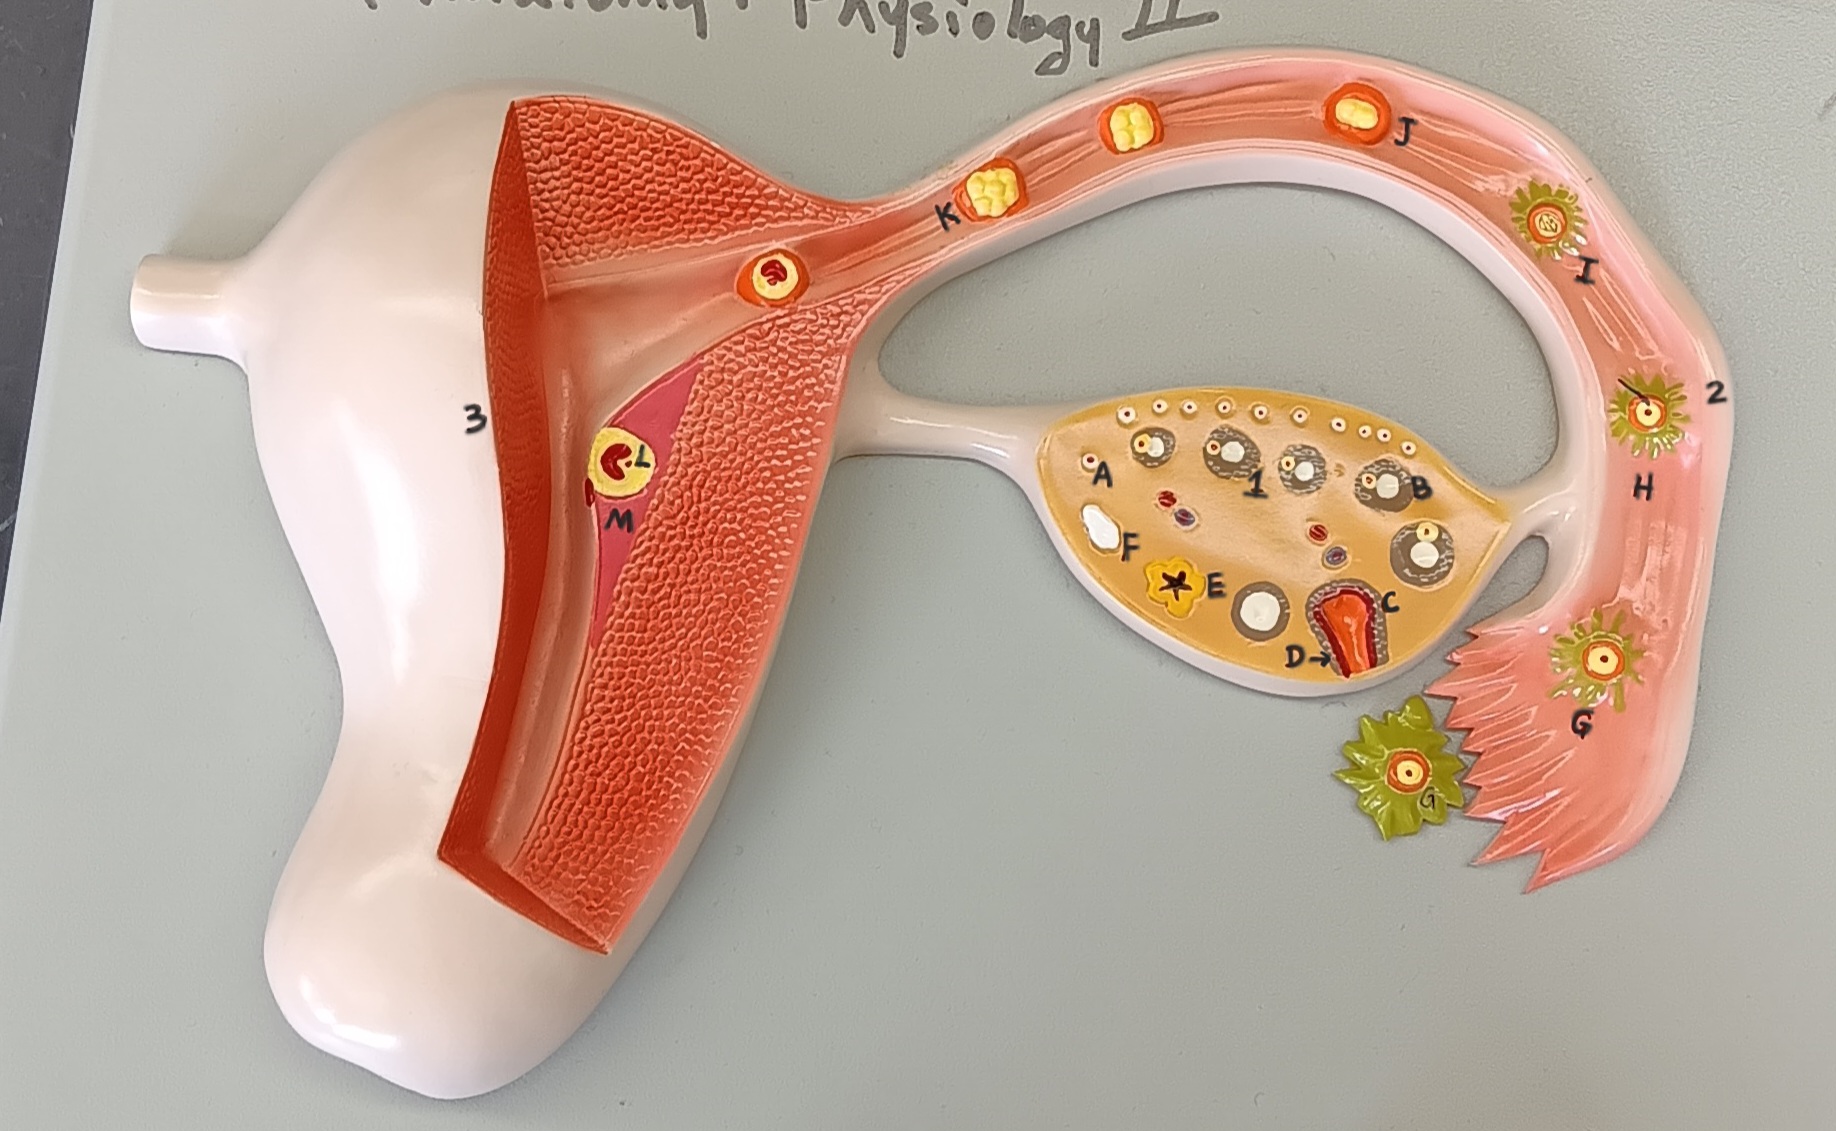

ovary

1

primordial follicle

a

secondary follicle

b

ruptured follicle

c

granulosa cells

d

corpus luteum

e

secondary oocyte

g

ovum

h

zygote

i

blastocyst

l

endometrium

m

corpus albicans

f

uterus

3

fallopian tube

2